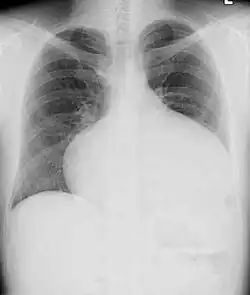

Abnormal chest X-ray as seen in a patient of atrial septal defect

Most individuals with a significant ASD are diagnosed in utero or in early childhood with the use of ultrasonography or auscultation of the heart sounds during physical examination. Some individuals with an ASD have surgical correction of their ASD during childhood. The development of signs and symptoms due to an ASD are related to the size of the intracardiac shunt. Individuals with a larger shunt tend to present with symptoms at a younger age.

Adults with an uncorrected ASD present with symptoms of dyspnea on exertion (shortness of breath with minimal exercise), congestive heart failure, or cerebrovascular accident (stroke). They may be noted on routine testing to have an abnormal chest X-ray or an abnormal ECG and may have atrial fibrillation. If the ASD causes a left-to-right shunt, the pulmonary vasculature in both lungs may appear dilated on chest X-ray, due to the increase in pulmonary blood flow.[36]